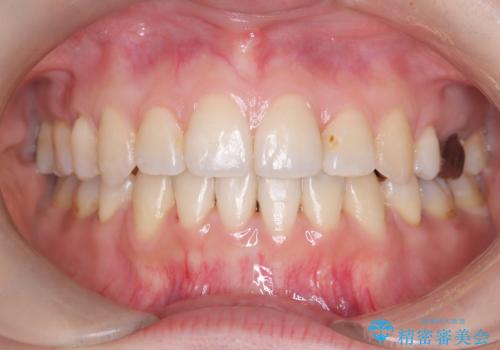

【ワイヤー矯正】口元を下げたい、下の歯の凹凸を無くしたい

- 主訴:口元を下げて前突感を無くしたい、下の歯の凹凸も無くしたい

骨格的顎の変位を認めたため、顔貌に対しピッタリ上下の歯の正中を合わせることは難しいと説明し、上下左右計4本小臼歯を抜歯しワイヤー矯正治療を行いました。